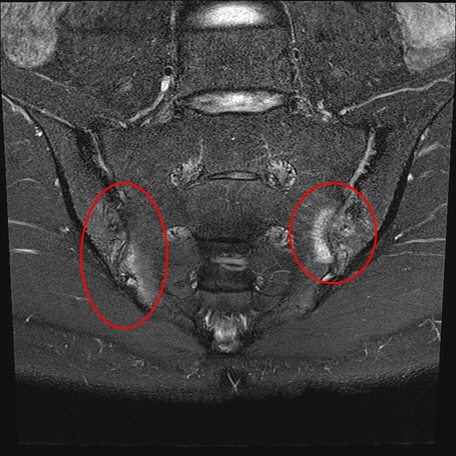

[스포츠조선 장종호 기자] 강직척추염은 만성 연증성 질환인 척추관절염 중 하나다. 척추나 관절 외에 눈, 피부, 위장관 등 신체 여러 장기에서 질환을 나타낼 수 있어 단순한 근골격계 질환이 아닌 전신 질환에 해당한다. 영상검사 결과 천장관절염(척추 아래 뼈인 천골과 골발뼈인 장골이 만나는 관절에 염증이 생기는 질환)이 있고 척추관절염의 정의에 부합하는 경우 강직척추염이라 정의한다.

이주하 교수는 "강직척추염이 초기에는 허리 디스크와 유사한 증상을 보여 오진하기 쉽다"며 "경험있는 류마티스 전문의가 증상을 감별하고 적절한 영상검사를 시행해 천장관절염을 발견하다면 조기진단이 가능하다"고 덧붙였다.